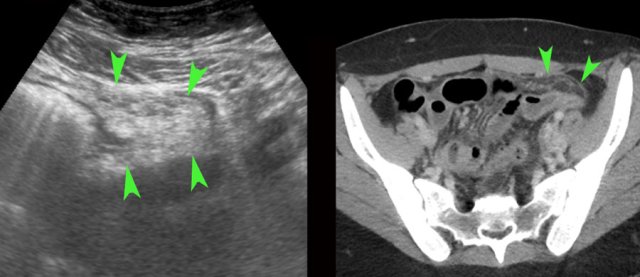

TOA case 4 (infected endometriotic cysts)

These images are of a 29-year old woman, suspected for appendicitis. CRP 185, WBC 17.

US shows a normal compressible appendix, thereby excluding appendicitis.

Large, thick-walled, septated cystic structures, filled with debris-like material, were found on both sides of the uterus (ut.), touching each other posteriorly (“kissing ovaries”).

This is somewhat suspect for bilateral infected endometrotic cysts.

The patient was treated with antibiotics and laparoscopic drainage.

There was a protracted course, but eventually regression of the abnormalities.

An MRI six months later, demonstrated all the signs of deep infiltrating endometriosis, also invading the rectum, thereby confirming the diagnosis of endometriosis.